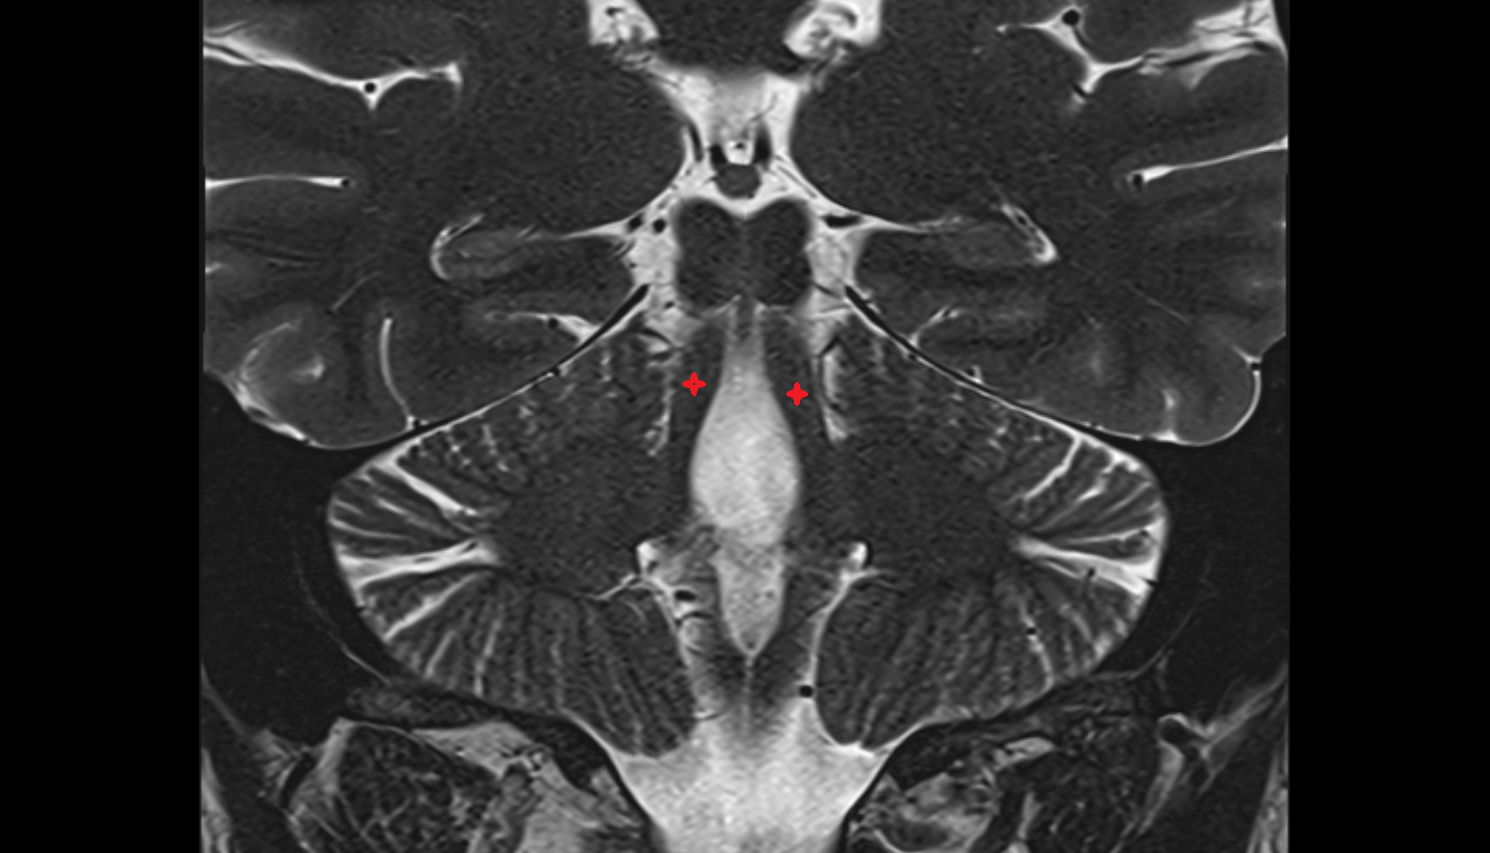

- Dentate nucleus